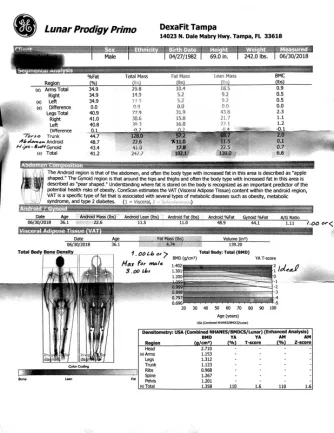

Heres a dexascan. It was alarming. I was working out with my trainer (on a pretty strict monitored diet around 1800 calories macro based) for almost 4 months when this was taken. It’s my trainer who prompted me to get this done as well as some bloodwork since the scale isn’t moving much (a couple lbs up and down) which floored him since he sees how hard I’ve been working out as well as what I’ve been consuming. Seems as if there is some internal factors preventing positive gains.

Heres a dexascan. It was alarming. I was working out with my trainer (on a pretty strict monitored diet around 1800 calories macro based) for almost 4 months when this was taken. It's my trainer who prompted me to get this done as well as some bloodwork since the scale isn't moving much (a couple lbs up and down) which floored him since he sees how hard I've been working out as well as what I've been consuming. Seems as if there is some internal factors preventing positive gains.